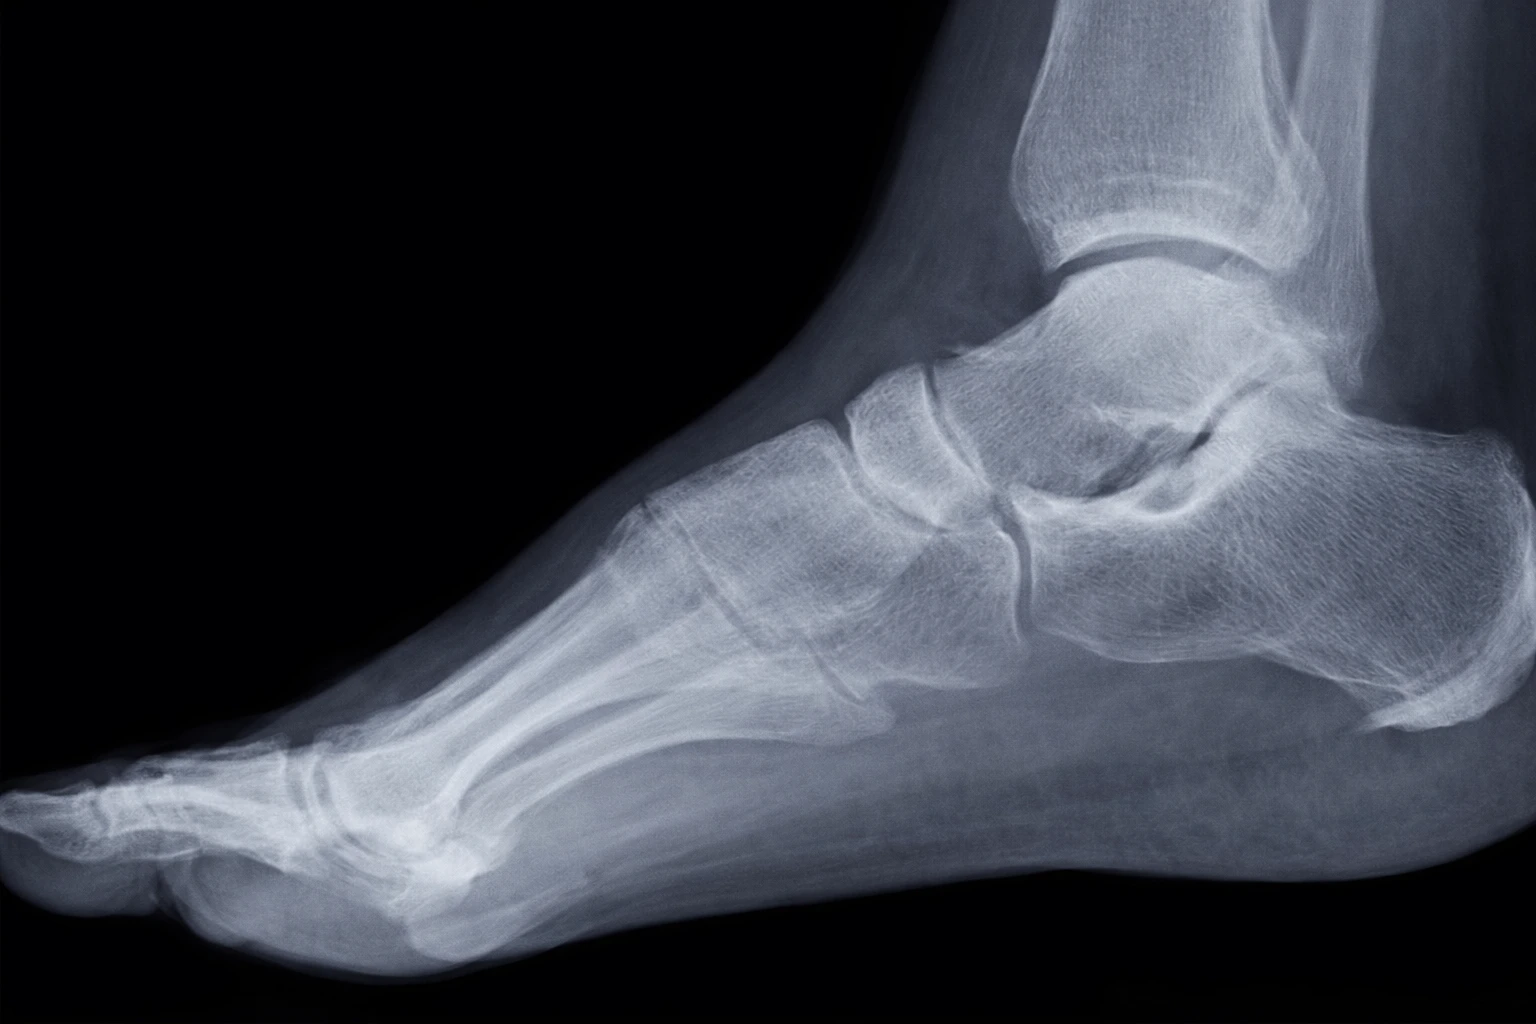

X-ray

Radiographic signs of heel spur (or plantar fasciitis) may include specific features that help healthcare professionals confirm the diagnosis. However, it is important to note that the presence of a heel spur on the x-ray does not always correspond to the severity of the symptoms experienced by the patient. Some individuals may have a heel spur without experiencing significant pain, while others may have severe pain without it necessarily being related to the presence of a heel spur. Here are some possible radiographic signs:

- Heel spur: X-ray may reveal the presence of a bone spur at the calcaneus (heel), which is often the classic feature of heel spur. However, not all patients with plantar fasciitis have a heel spur.

- Thickening of the plantar fascia: An x-ray may show thickening of the plantar fascia, indicating inflammation or excessive tension in the tissue.

- Enthesopathy: Enthesopathy is a condition characterized by inflammation at the enthesis, the area where the tendon or ligament attaches to the bone. In the case of heel spurs, the enthesis of the plantar fascia may show signs of inflammation.

It is essential to note that the diagnosis of plantar fasciitis does not rely solely on radiographic findings. The clinical picture, including the symptoms reported by the patient, the physical examination and sometimes additional tests such as ultrasound, can also be used to make an accurate diagnosis.